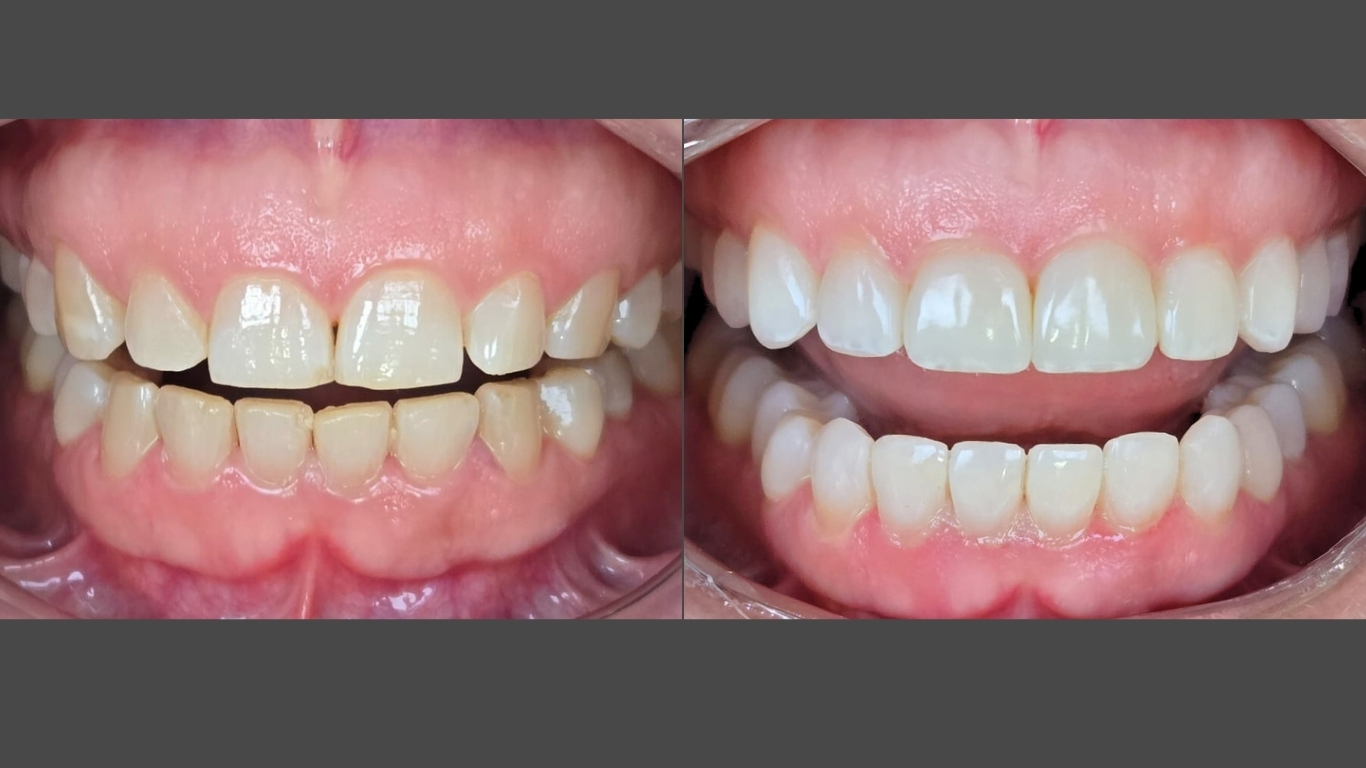

Caso Clínico 1